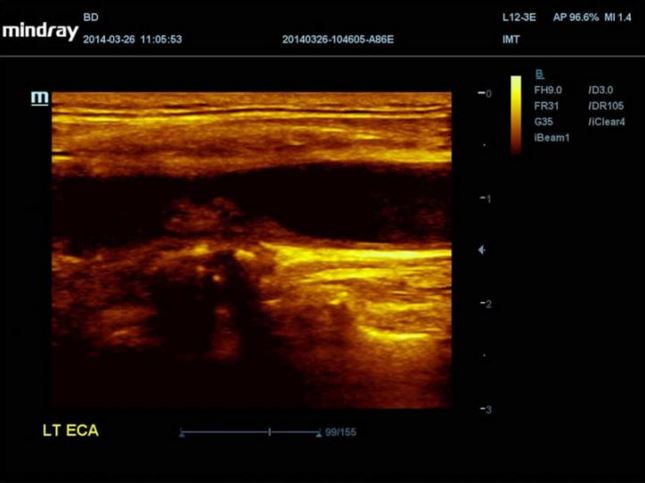

MINDRAY DC-70

Produkt wycofany z produkcji.

Aparat DC-70

Aparat DC-70 daje znacznie więcej. Jego unikalne sterowanie dotykiem i gestem zostało zaprojektowane w taki sposób, by usprawnić płynny obieg czynności. Czystość obrazu uzyskiwana dzięki innowacyjnej technologii głowic w aparacie DC-70 pozwoli wykryć anomalie lub nawet niewielkie zmiany. Narzędzia ułatwiające użytkowanie, obejmujące między innymi wiele pakietów do automatycznych pomiarów pomagają zredukować czas skanowania, standaryzować protokoły badań, zwiększyć produktywność i otoczyć pacjenta jeszcze lepszą opieką.